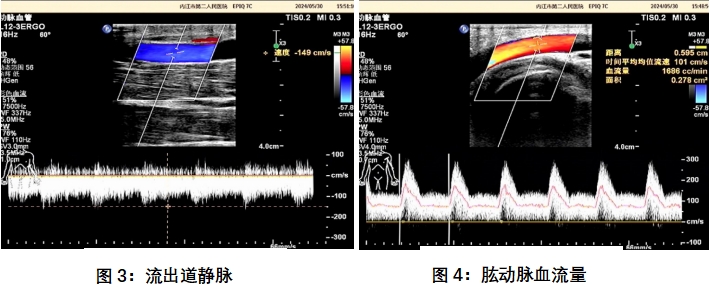

(3)使用超声设备:医生使用超声高频探头对动静脉内瘘术后循环通路进行扫查。超声医生通过二维图像及彩色多普勒图像,可以观察到血管的内径、血流的速度及方向。

(4)动静脉内瘘超声评估的内容:评估内瘘流量是否充足、管腔大小、深度、有无狭窄、血栓、破裂、隔膜、内膜增生、动脉瘤、血肿等

(5)结果分析:内瘘成熟的标准:在连续4周的时间内,75%的透析疗程都能用两针重复插管的瘘管。超声标准:血流量>500ml/min,静脉血管直径≥5mm,静脉距离体表深度<6mm。检查后,超声医生将对获得的超声图像和数据进行分析,并给出专业的评估和建议。